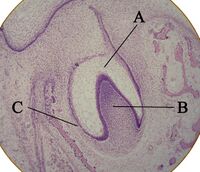

Histologic slide showing a tooth bud.

A: enamel organ

B: dental papilla

C: dental follicle

The tooth germ is an aggregation of cells that eventually forms a tooth.[2] These cells are derived from the ectoderm of the first pharyngeal arch and the ectomesenchyme of the neural crest.[1][3][4] The tooth germ is organized into three parts: the enamel organ, the dental papilla and the dental sac or follicle.

The enamel organ is composed of the outer enamel epithelium, inner enamel epithelium, stellate reticulum and stratum intermedium.[2] These cells give rise to ameloblasts, which produce enamel and become a part of the reduced enamel epithelium (REE) after maturation of the enamel. The location where the outer enamel epithelium and inner enamel epithelium join is called the cervical loop.[1] The growth of cervical loop cells into the deeper tissues forms Hertwig Epithelial Root Sheath, which determines the root shape of the tooth. During tooth development there are strong similarities between keratinization and amelogenesis.[5][6] Keratin is also present in epithelial cells of tooth germ [7] and a thin film of keratin is present on a recently erupted tooth (Nasmyth's membrane or enamel cuticle).[8]

The dental papilla contains cells that develop into odontoblasts, which are dentin-forming cells.[2] Additionally, the junction between the dental papilla and inner enamel epithelium determines the crown shape of a tooth.[1] Mesenchymal cells within the dental papilla are responsible for formation of tooth pulp.

The dental sac or follicle gives rise to three important entities: cementoblasts, osteoblasts, and fibroblasts. Cementoblasts form the cementum of a tooth. Osteoblasts give rise to the alveolar bone around the roots of teeth. Fibroblasts are involved developing the periodontal ligament which connect teeth to the alveolar bone through cementum.[9]